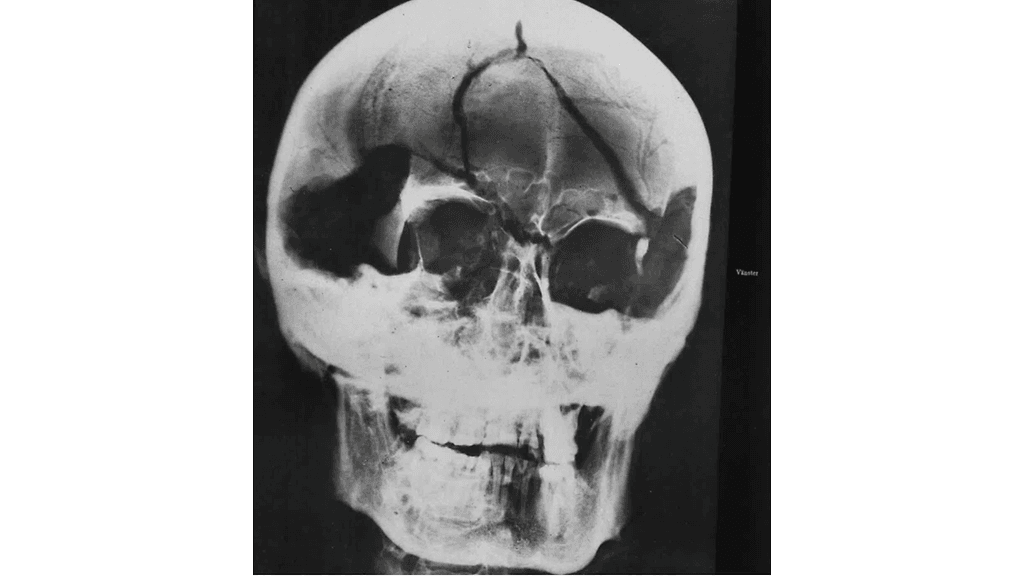

Tutkijoiden mukaan Kaarle XII:n kuolinsyytä on tutkittu aiemmin kolmessa ruumiinavauksessa vuosina 1746, 1859 ja 1917. Viimeisessä ruumiinavauksessa jopa röntgenkuvattiin kuninkaan muumioituneet jäänteet, jotka on haudattu Riddarholmenin kirkkoon Tukholmaan.